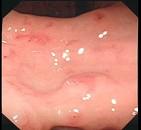

问题 患者女性,45岁,吞咽阻挡感半年,伴咽下胸骨后疼痛,低热,咳嗽,乏力,查体,消瘦貌,浅表淋巴结无肿大,心肺查体无明显异常,胃镜检查如图,该患者最有可能是下列哪种疾病 ( )

选项 A、食管结核 B、食管憩室 C、食管贲门失弛缓症 D、食管息肉 E、胃食管反流病

答案 A